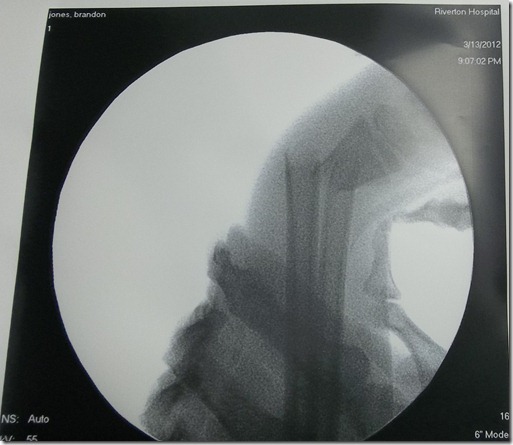

Watch the slide show to see how this adventure played out. Brandon was the photographer of the pictures of the girls and I playing basketball. This all happened in 5 min after dinner. Brandon had been working hard to really master the rip stick all evening and in just a couple minutes down he went. We went outside about 6:50pm and we were headed to the Insta Care at 7:05pm then sent right from there to Riverton Hospital. The hospital staff and the doctors and surgeon were AMAZING!!! We finally arrived back home around 12:30am and Brandon was in bed asleep by 1am. At the insta care his fingers were blue because his main artery in his hand was being pinched by the break and the artery was spasaming. Very scary!!! The nurse sent us directly on to the hospital since his break was too bad and complex and would require a surgeon to set it. He had been given a priesthood blessing by his Dad and Bishop Dalton before leaving for the hospital and that brought us a lot of comfort. Brandon is one very special and very BRAVE boy. We love him so much and I look forward to really serving him a lot during the next 8 weeks as his arm heals.

His broken arm with the orthopedic surgeons hand holding it. OUCH!!!

One very talented orthopedic surgeon man handled his bad break and got it perfectly back in place!